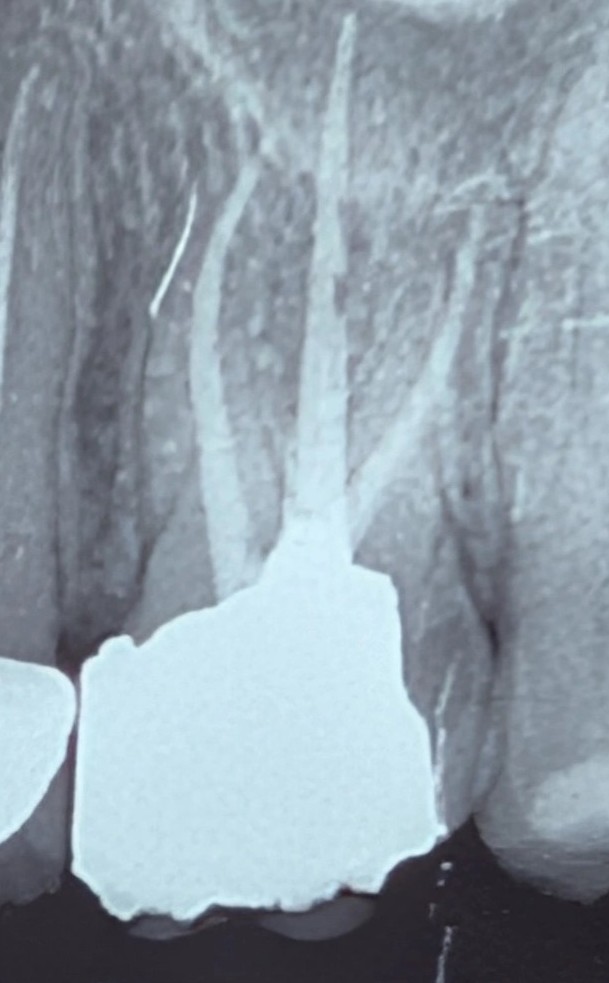

بیمار با درد مبهم در ناحیه مزیال دندان ۶ بالا سمت چپ مراجعه کرد. درد بیشتر به صورت درد مبهم بیندندانی توصیف میشد.

در رادیوگرافی، یک ترمیم آمالگام وسیع مشاهده میشد که کانتور آن در ناحیه مزیال و در کنار استخوان نامناسب بود.

شکل ترمیم عملاً فضای طبیعی ناحیه اینترپروگزیمال را مختل کرده و با توجه به موقعیت آن، احتمال تجاوز به بیولوژیک ویدث مطرح میشد.

علاوه بر این، تحلیل خفیفی از کرست استخوانی در همان ناحیه دیده میشد که میتواند نشانهای از پاسخ بافت پریودنتال به همین تجاوز باشد.